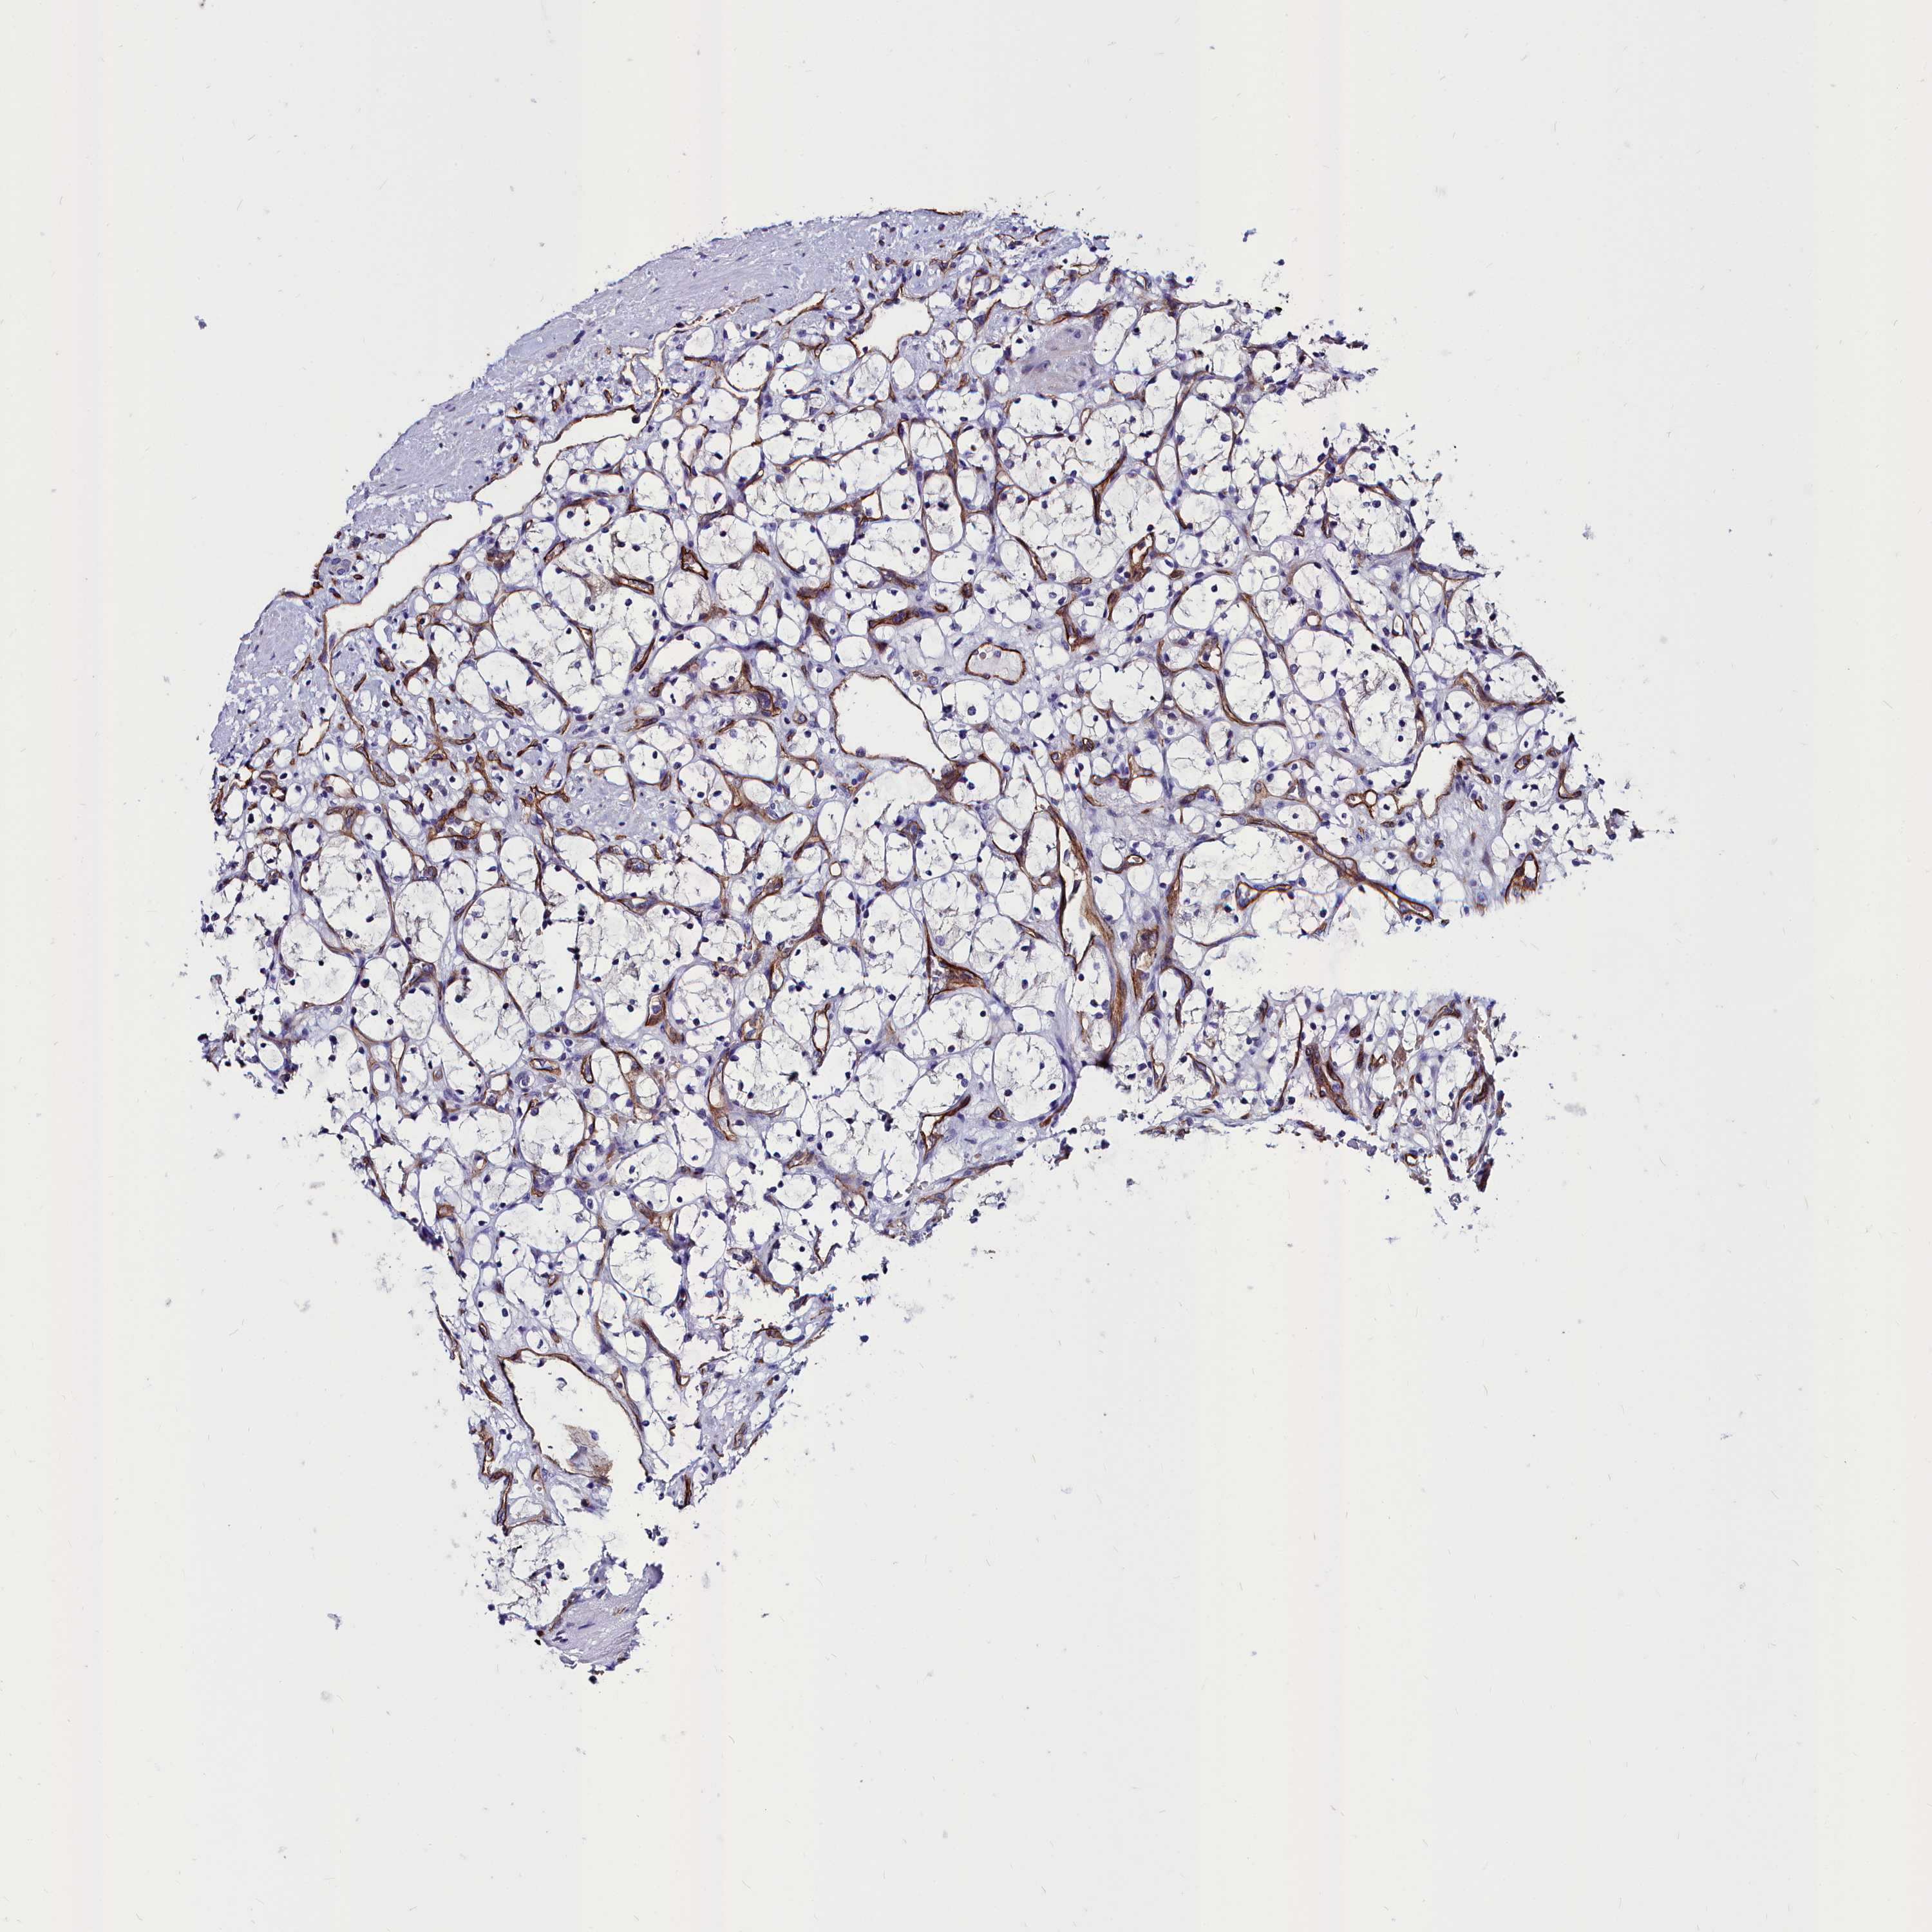

CANCER RENAL CANCER Show tissue menu

KICH TCGA KIRC TCGA KIRC VALIDATION KIRP TCGA PROTEIN RCC CPTAC PROTEIN EXPRESSION